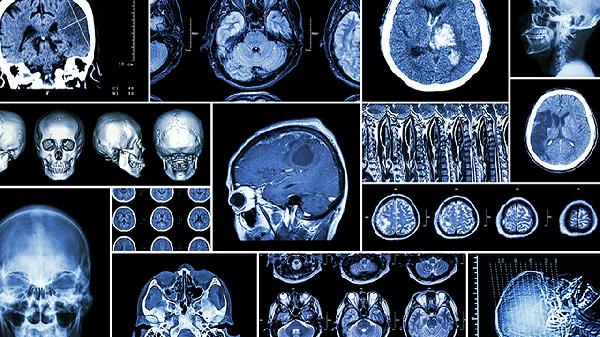

脑血栓后遗症患者需坚持长期康复训练,家属应协助进行日常肢体活动与语言交流。饮食宜选择易消化、富含优质蛋白的食物,如鱼肉、蛋羹等,避免进食过硬或粘性食物。定期复查头颅CT或核磁共振,监测病情变化。保持规律作息,避免情绪激动,戒烟限酒以预防复发。若出现新发症状或原有症状加重,应立即就医。